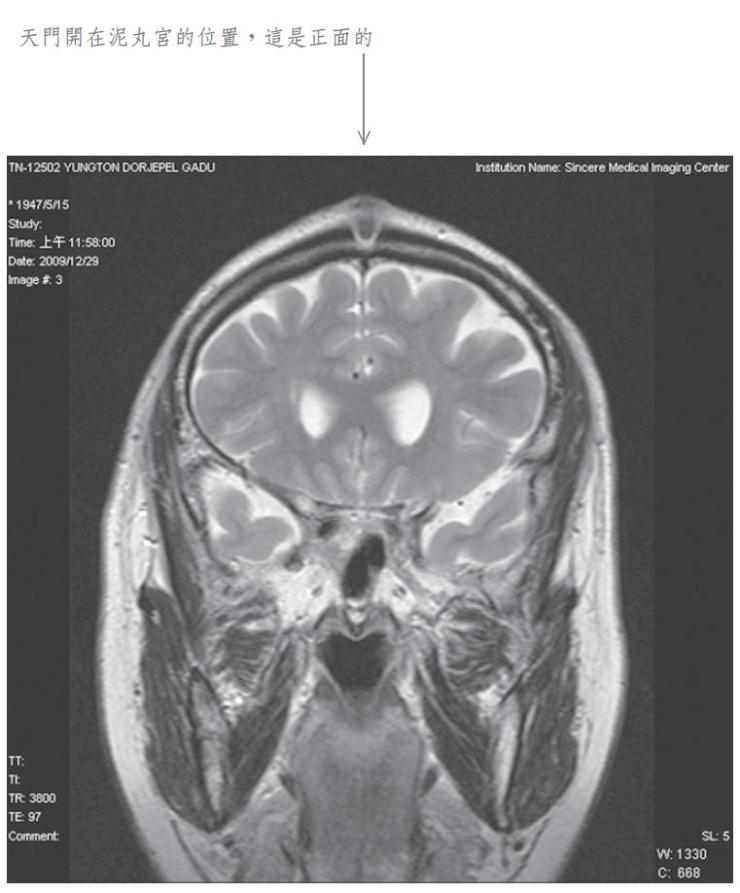

當我將此種修法中發生之覺受稟報佛陀師父時,佛陀師父又為我傳了秘密口訣。經過一段時日,佛陀師父在公開開示的法音帶中,才提到我曾經修法達到化身境的初級,即是素化身的意思。為了讓眾生明瞭佛法的偉大,事隔多年之後,我特別於二零零九年十二月廿九日,到中心綜合醫院安排磁振造影(MRI)頭部的攝影檢查,結果發現泥丸宮的部位出現一個1.5公分寬深的開口,同時拍下了有一股神識出氣衝出頭部的實況。負責檢查的醫生非常驚訝稱奇,但無法解釋其原因,因而將它歸因於非人之所為。我其實非常清楚,我的神識化身本來就是從這裡出入的,以下是在醫院MRI檢查的掃瞄片。